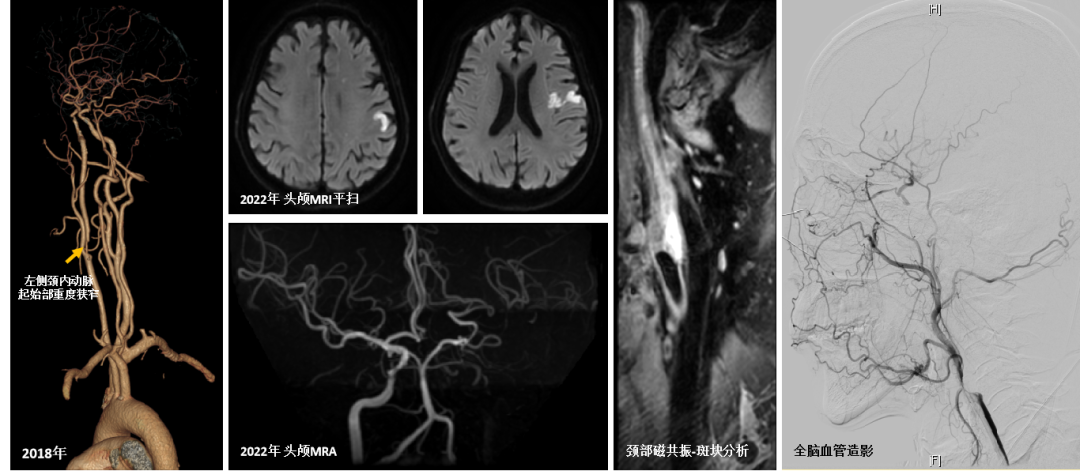

4年前,老赵因一次事故,被转运到清华长庚并诊断为蛛网膜下腔出血,医生在排查颅内出血原因的过程中,发现他左侧颈内动脉起始部重度狭窄。颅内出血病情平稳后,尽管患者遵医嘱使用脑血管病预防药物,可颈部斑块仍然逐年增大,最终在2个月前发生脑梗。

紧急来到清华长庚后,神内副主任医师李珺发现患者有从颈动脉起始段到眼动脉段的长节段慢性血管闭塞。管腔内的出血性斑块,印证了本次脑梗正是由于颈内动脉起始处不稳定的大斑块突然崩解碎裂所致。

2018年头颈CTA示左侧颈内动脉起始部重度狭窄/2022年3月头颅MRI显示左侧颈内动脉供血区多发脑栓塞病灶,头颅MRA可见左侧颈内动脉全程闭塞,全脑血管造影可见左侧颈内动脉闭塞